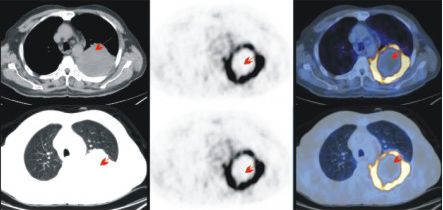

查體發(fā)現(xiàn)右肺上葉小肺癌,直徑0.6cm。術(shù)后病理:中分化腺癌。